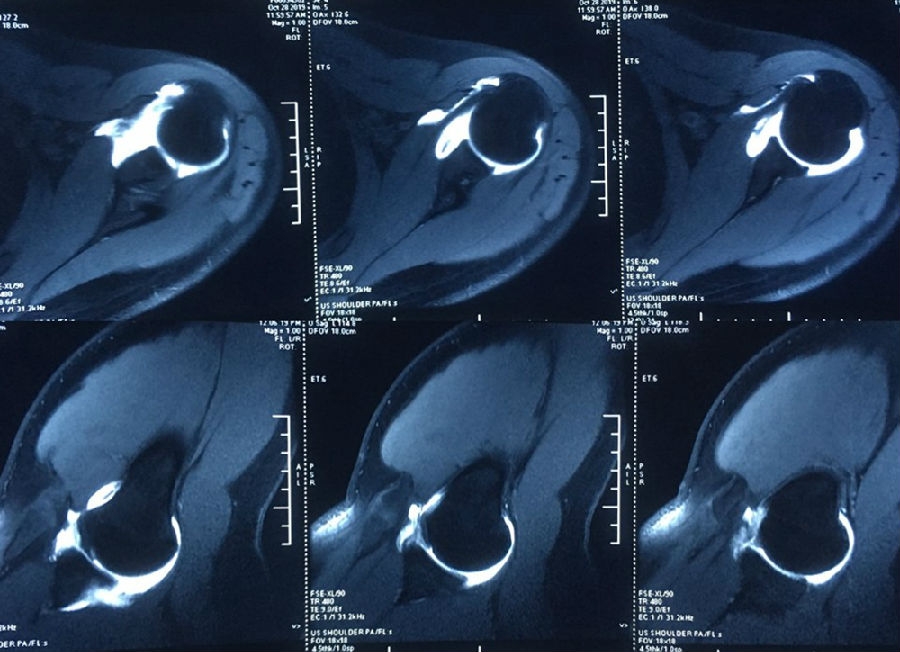

图42-43、视频17 术前查体,ASES评分57分,ISIS评分4分,Beighton评分2/9分

图44 术前MRI

图45 CT D=26mm d=8mm(上患侧,下健侧)

图46 CT d/D=30.7% GT=0.83D-d=13.6mm Hill-Sachs损伤I级,骨缺损 >25%